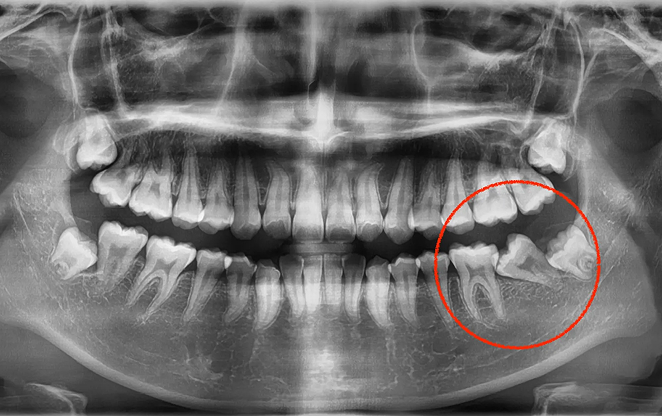

01

Before

After